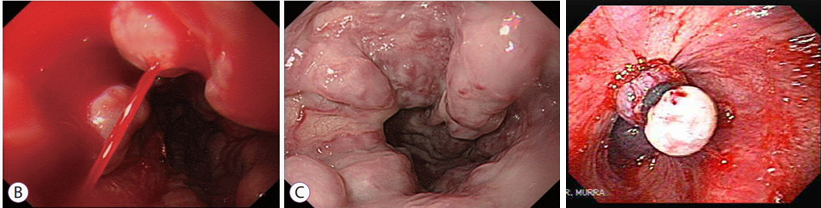

식도 정맥류 출혈

• 진단 : 식도 위 내시경

• 내시경 정맥류 결찰술(EVL)

위 정맥류 출혈

• 내시경 정맥류 폐쇄술(EVO) : 시아노아크릴레이트 주사